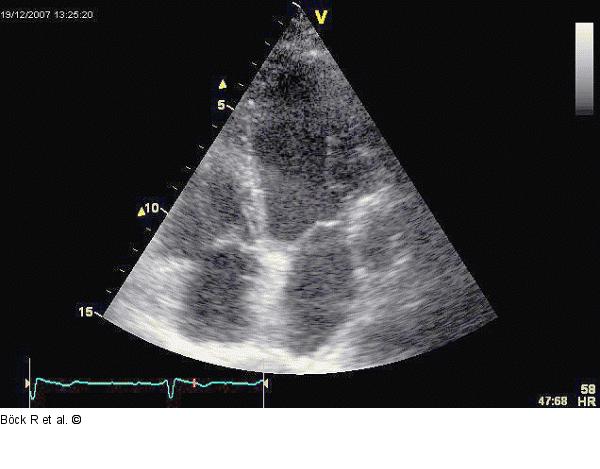

Abbildung 2: Sinus coronarius Vierkammerblick mit dilatiertem Sinus coronarius im linken Sulcus atrioventricularis |

Vierkammerblick mit dilatiertem Sinus coronarius im linken Sulcus atrioventricularis |